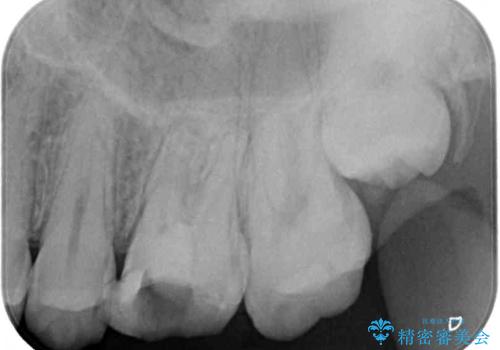

- ラバーダムや顕微鏡を用いた根管治療を希望されて、転院された患者様です。

前医にて神経を取り除いた処置を行った際、ラバーダムが使用されなかったとのことで転院されてきました。

根管治療を実施した後、フルジルコニアクラウンに補綴することとしました。